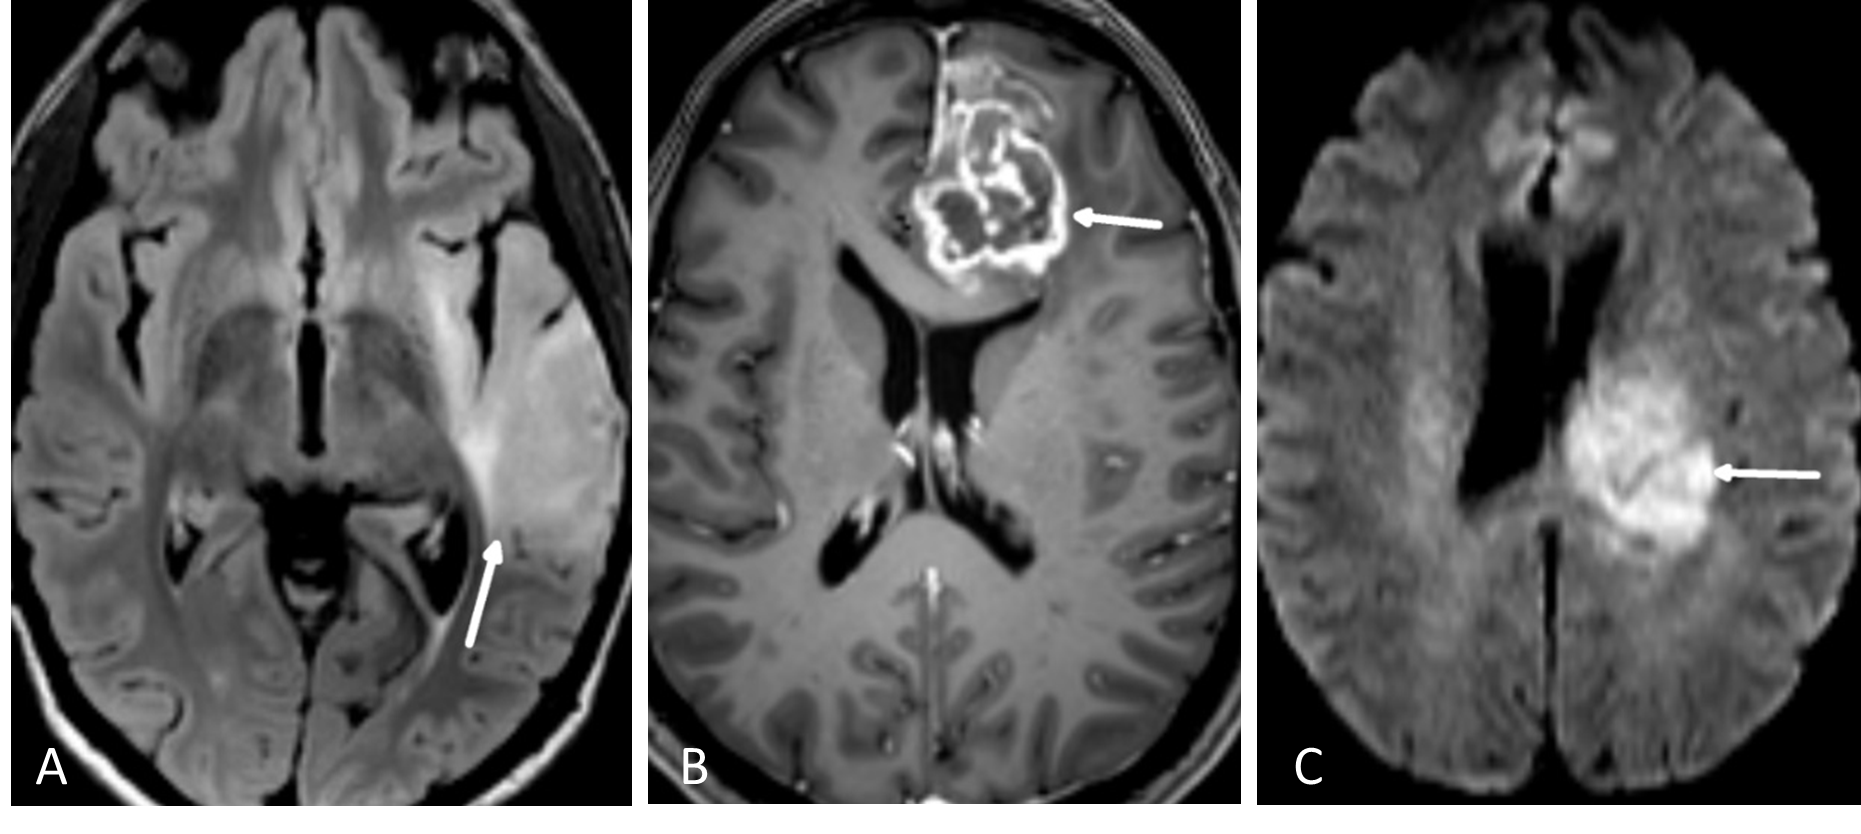

FLAIR er en MR-teknikk hvor man har eliminert det lyse signalet fra cerebrospinalvæsken i en T2-vektet bildesekvens (Figur 5.1). Man kan tro at når signalet i cerebrospinalvæsken undertrykkes blir også vann i en tumor svart. Det er imidlertid forskjell på MR-egenskapene til såkalt fritt vann (som i cerebrospinalvæske) og såkalt bundet vann som interagerer med blant annet makromolekyler i cellemembraner (som i en tumor). FLAIR-sekvensen er laget slik at det bare er det frie vannet som undertrykkes, mens bundet vann i patologiske lesjoner fortsatt lyser opp. En hjernetumorprotokoll vil alltid inneholde en FLAIR-sekvens, vanligvis som et 3D-volum som kan rekonstrueres i valgfrie bildeplan. Særlig på lavgradige, diffust infiltrerende svulster er FLAIR den mest sensitive bildesekvensen.

På T1-vektede MR-bilder av hjernen er cerebrospinalvæsken svart, fett i benmarg og underhud er lyst, mens hvit hjernesubstans er lysere enn grå substans. De mest brukte MR- kontrastmidler er gadolinium-chelater som gis intravenøst. Vev som tar opp kontrastmidlet får høyere signal (blir lyst) på kontrastforsterkede T1-bilder. MR-kontrastmidler krysser ikke en intakt blod-hjerne-barriere. Høygradig maligne hjernesvulster (CNS WHO grad 3-4), metastaser og meningeomer vil som regel lade opp kontrast, mens lavgradige nevroepiteliale svulster (CNS WHO grad 1-2) ofte ikke har kontrastopptak (Figur 5.1). Det er dog ingen absolutt sammenheng mellom kontrastopptak og graden av aggressivitet i svulsten. Alle tumorprotokoller inneholder T1-sekvenser før og etter intravenøs kontrast, enten som bildeopptak i transversal- og koronalplan, eller som et 3D-volumopptak som rekonstrueres i valgfrie bildeplan. Det sistnevnte er nå det vanligste. Det er et viktig poeng at ikke alt som lyser opp på T1-bilder er kontrastopptak, for eksempel har også blod og fett høyt T1-signal. For å unngå feiltolkning inneholder derfor tumorprotokollen også en T1-serie før kontrastinjeksjon.

Bildekontrasten på diffusjonsbilder avhenger av vannmolekylenes mobilitet i vevet. Mobiliteten til vannmolekylene er høy i rommet mellom cellene, men lav inne i cellene. Hjernesvulster med høy celletetthet som lymfomer og medulloblastomer, har lav diffusjon. Høygradige gliomer (CNS WHO grad 3 og 4) har høyere celletetthet og dermed lavere diffusjon enn gliomer med lavere malignitetsgrad (Figur 5.1). Diffusjonsvektede bilder er også nyttige for å skille mellom nekrose og abscesser.